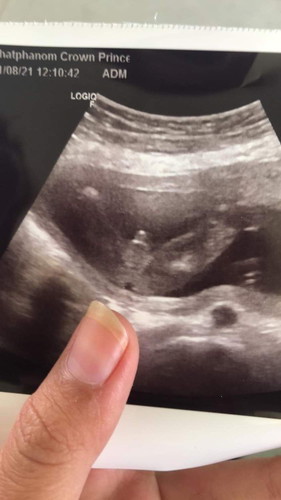

#แบบนี้ผช ชัวร์ไหมคะแม่ๆ 🥺🙏 รูปนี้ไปซาวด์ได้ตอน 3-4 เดือน แต่ตอนนี้แม่ตั้งครรภ์ได้34+3 แต่ใครๆเห็นท้อง ก็มีแต่คนบอกว่า ผญ บางคนก็บอกว่าอาจจะเป็นสานสะดือก็ได้ แต่คุณหมอก็บอกว่า ผช ชัวร์100%

Silverแม่ of 1 สุดน่ารัก หนุ่มน้อย